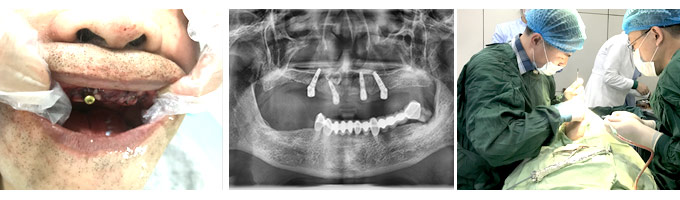

由于林老伯和郑老伯属于全口缺牙,缺牙时间久,牙槽骨的状态并不乐观,所以郭晓强院长为打算利用康贝佳“ALL-ON 4”技术来帮两位老人进行牙齿修复手术。据郭晓强院长介绍,ALL-ON-4技术称为针对全口无牙颌者、疑难种植牙、高龄种植牙、即刻种植即刻负重的先进技术。只需4颗种植体就可以完成半口牙的修复,以此来完成缺牙的修复手术。

考虑到二位老人的年龄问题,郭晓强院长在术前也是做足了功夫,经过详细的口腔CT检查,又经过术前的方案模拟种植,郭晓强院长才走上手术台,借助计算机导靶定位设备与自己多年的临床经验,将种植体以精确到毫米的距离植入患者口中,将创口控制在2mm以内,实现了微创种植、即刻负重的手术效果。不到两小时,先后为林老伯和郑老伯完成了种牙手术。